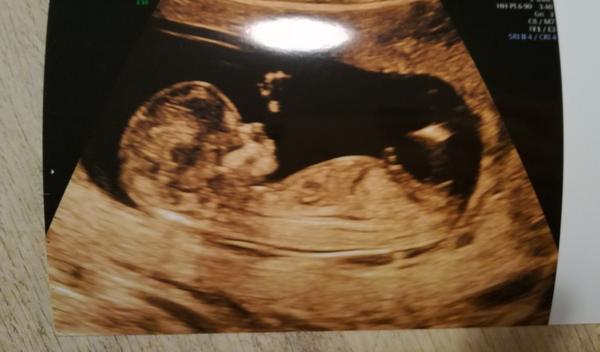

Ahoj holky, na konci července jsem byla na prvním screeningu a nezeptala jsem se na pohlaví, doktorka taky nic nezmínila. Ale pořád prohlížím fotku a snažím se z toho zjistit, co by to mohlo být, ale nic z toho nepoznám 😀 jsem hrozně zvědavá a na další utz jdu až v září. Prosím tipnete si, jestli něco vidíte.

@mrnousek121 Já tam bohužel nic nevidím, jak je fotka z boku. Tak se musím nechat překvapit na příštím ultrazvuku 🙂